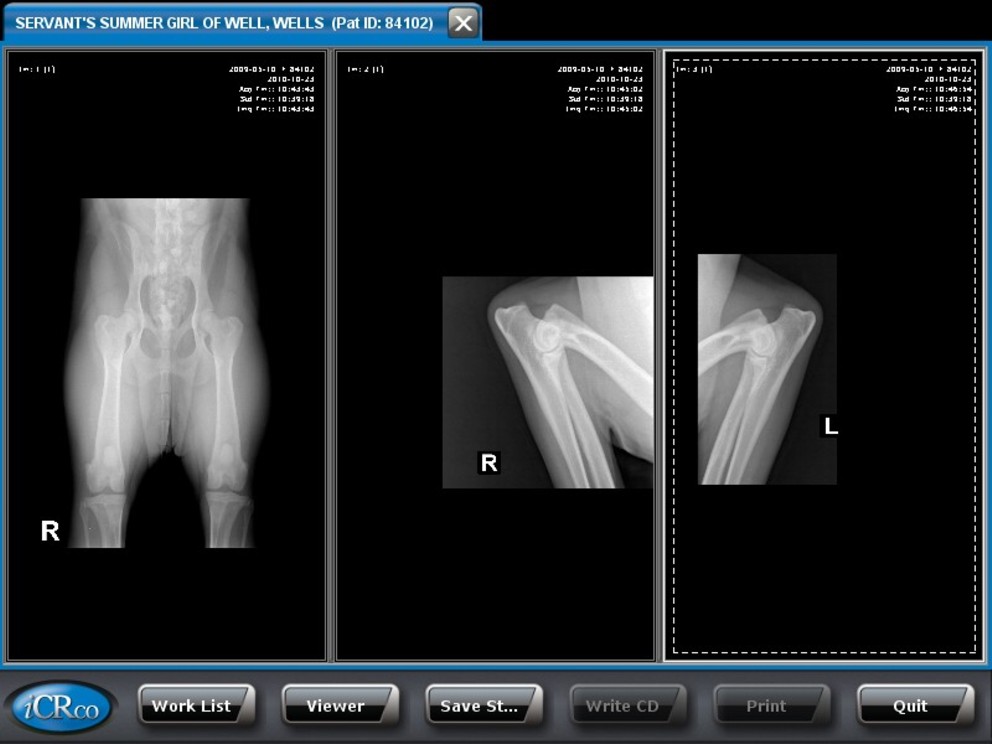

Summer's X-Rays

And OFA Prelim Report

She is Excellent on hips and elbows are normal...